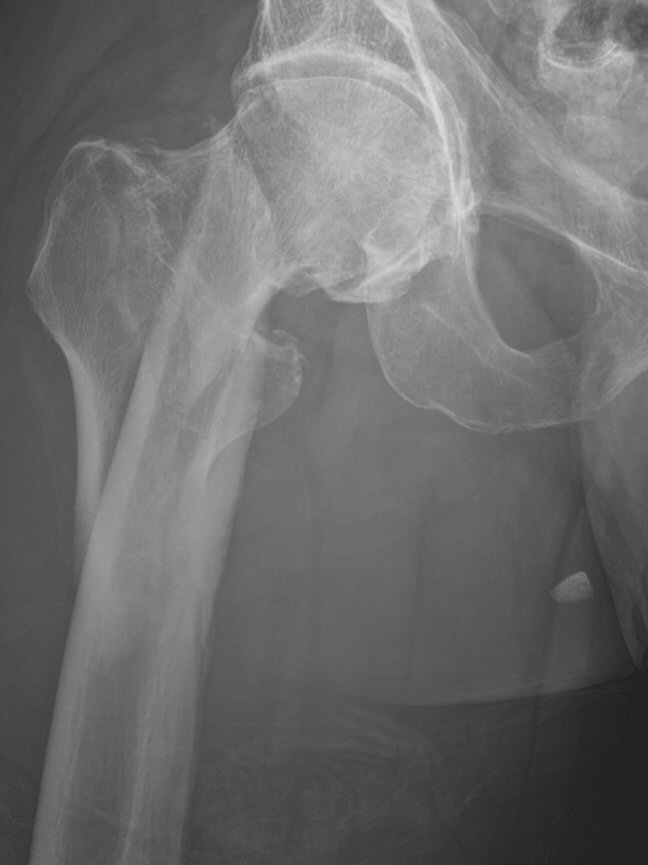

- Pertrokantär femurfraktur (PTFF): fraktur genom trokanterområdet

- Subtrokantär femurfraktur: laterala frakturlinjen går distalt om trokanter minor, ner till max 5 cm distalt om trokanter minor. I AO:s klassifikation finns inte begreppet subtrokantär fraktur, nedanför trokanter minor räknas det som diafysär fraktur.

Subtrokantär femurfraktur